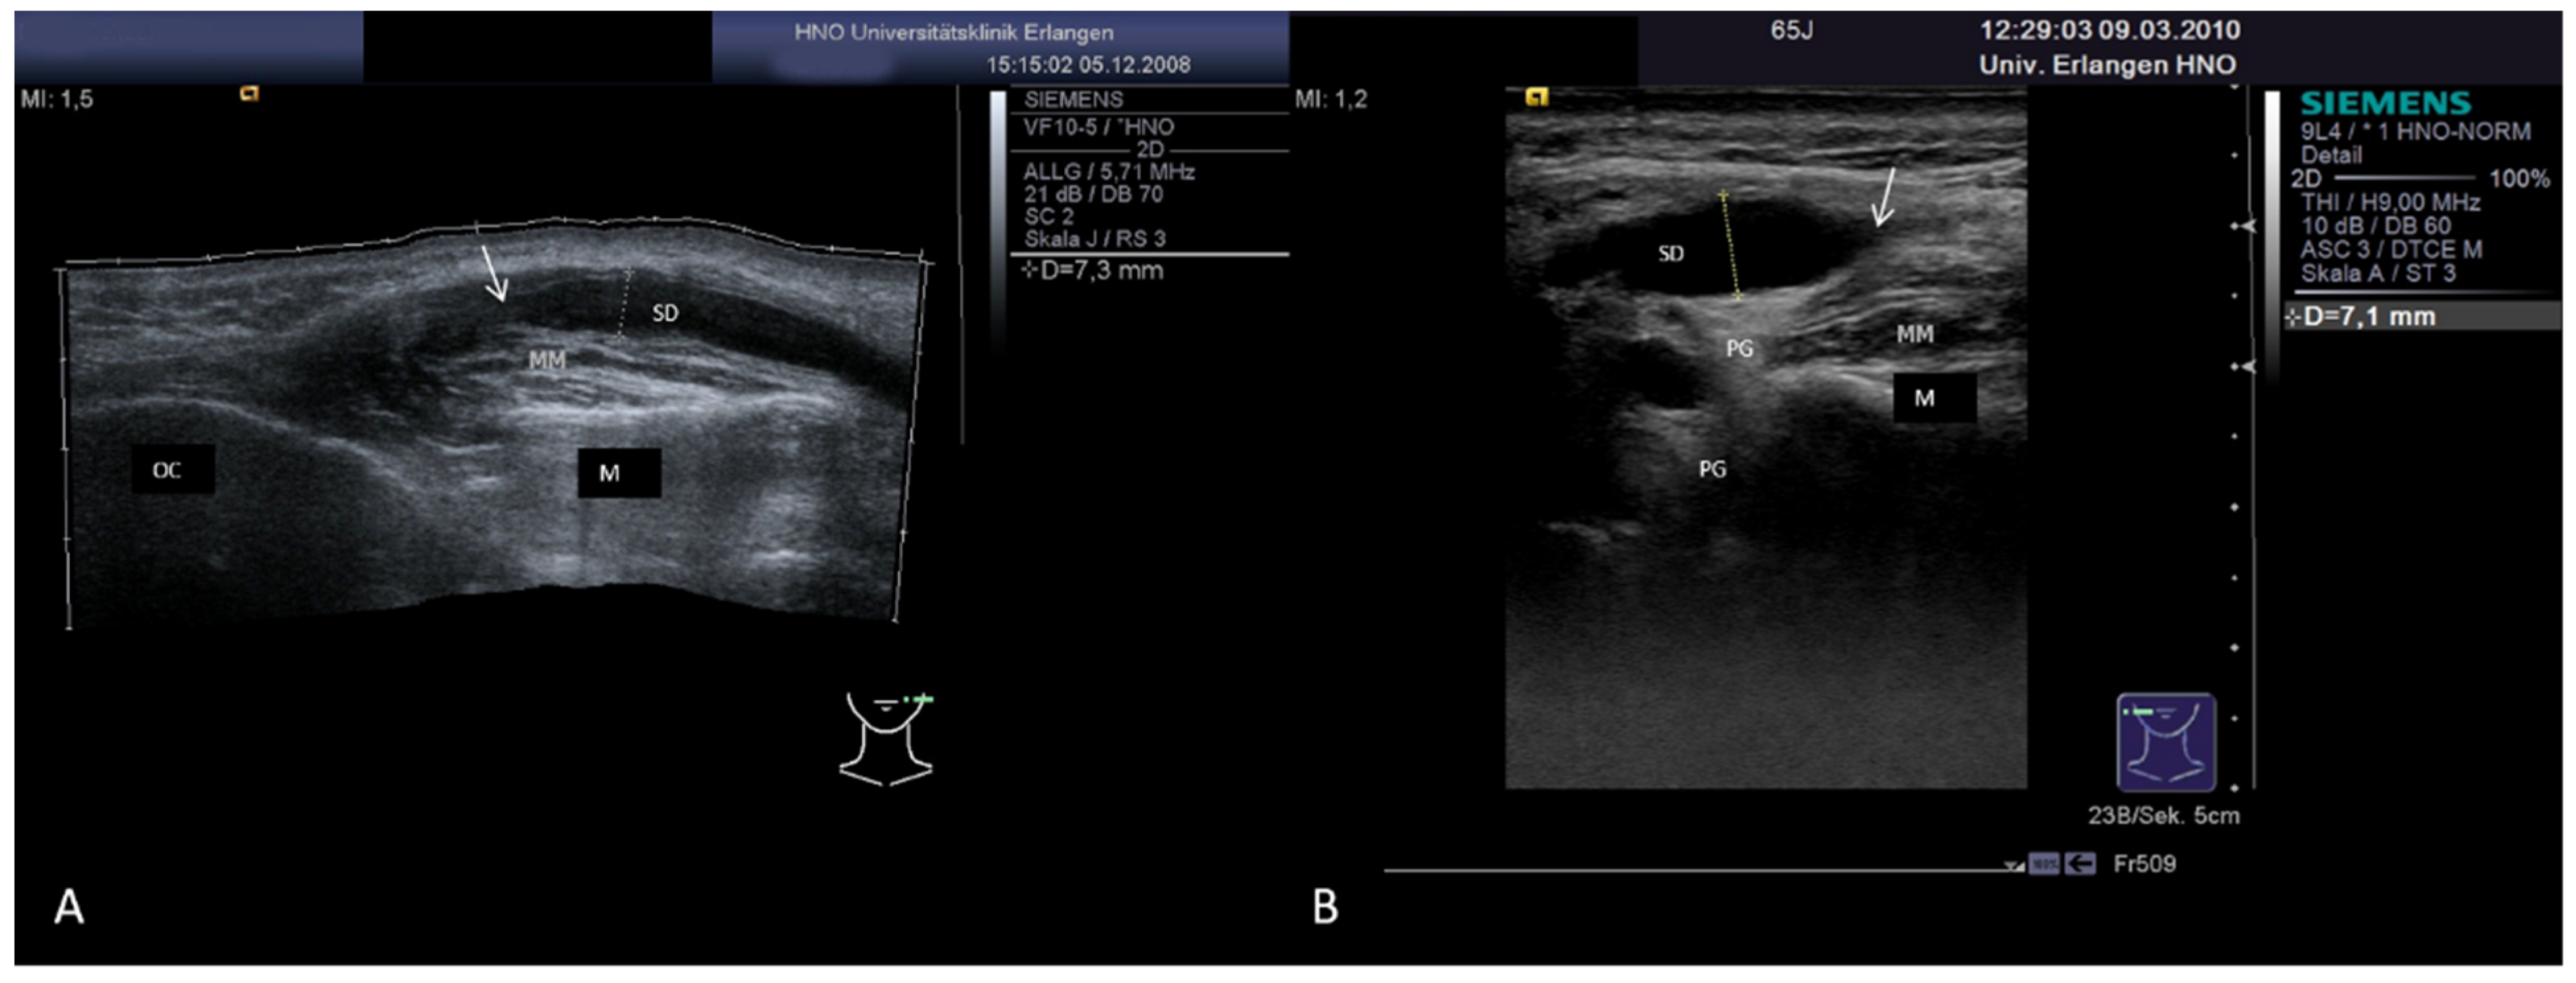

3.3.2. Obstructive Sialadenitis Caused by Sialolithiasis

3.3.3. Non-Sialolithiasis-Caused Unspecific Sialadenitis with Sialodochitis and/or Duct Stenosis with Primary or Secondary Obstruction

3.5. Ultrasound in Monitoring Gland Function at the Follow-up Examination in Inflammatory and Obstructive Salivary Gland Disease